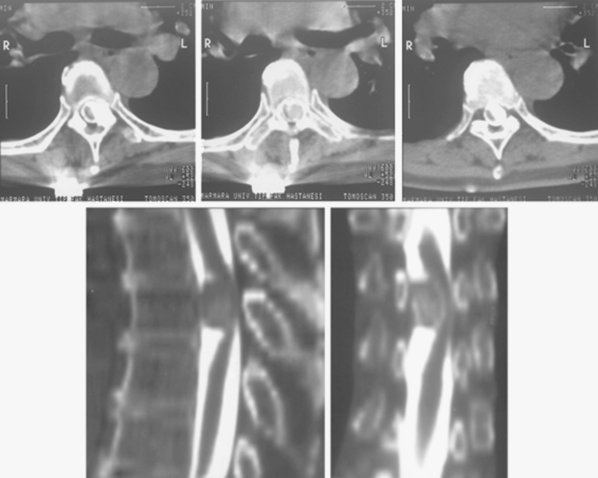

• 少見的脊髓腦膜瘤癥狀有哪些?如何治療?

少見的脊髓腦膜瘤癥狀有哪些?如何治療?

2020-04-22 18:10:26

位于C2椎體水平以下的腦膜瘤稱為脊髓 腦膜瘤 。腦膜瘤是二常見的腫瘤,僅次于神經(jīng)鞘腫瘤。脊膜瘤較常見的是完全的硬膜內(nèi)和髓外。然而,硬膜外延長(zhǎng)的...